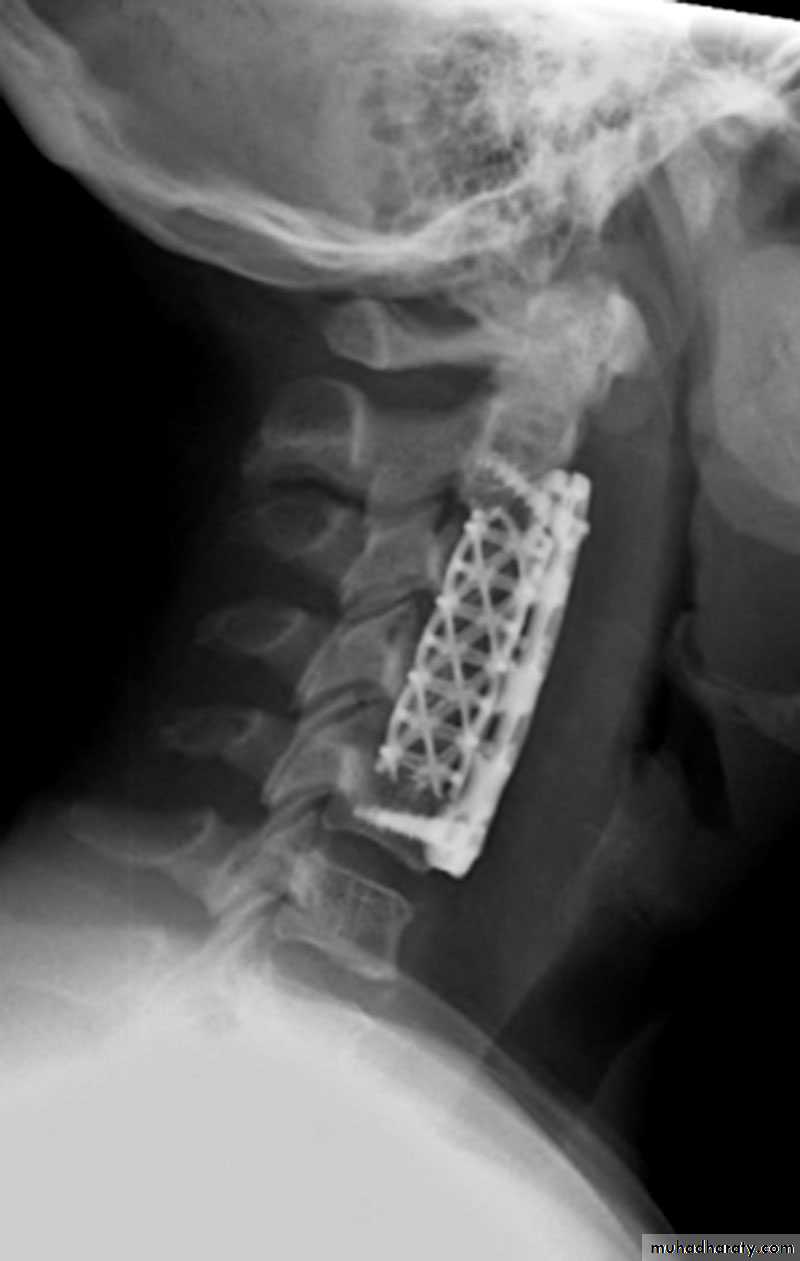

Operative treatment :

Ant. vertebral height loss > 50%.Canal compromise > 50%.

Kyphosis>20degrees.

Neural compression ( especially if progressive ).

Surgical options

Posterior FixationAnterior Fixation

Combination of both